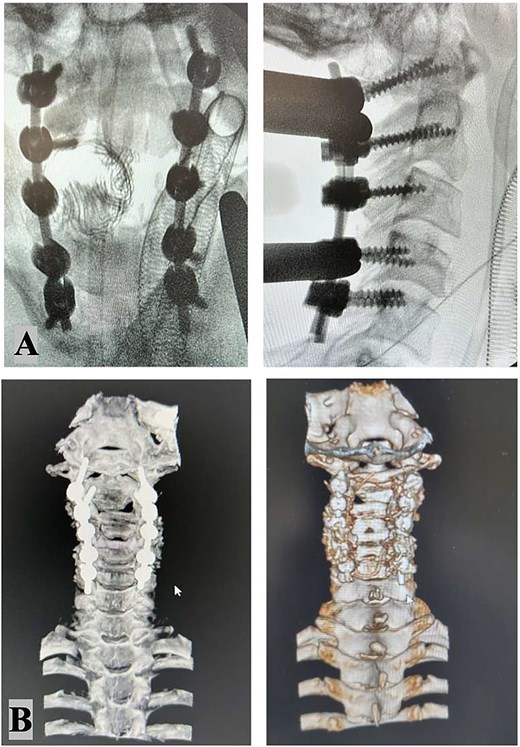

Intraoperative X-ray: Stable fixation and proper alignment of the cervical spine after C1–2–3–4–5 bilateral screw placement (A). Postoperative CT scan imaging confirmed successful realignment and structural integrity (B).

The intricate nature of the injury necessitated thorough evaluation of surgical options, with careful consideration given to systemic, vascular, mechanical, and neurological parameters. The surgical options included external traction, anterior cervical approach, posterior cervical approach, and a combined anterior–posterior approach. Given the presence of bilateral carotid artery dissections, which rendered the vessels exceptionally delicate, an anterior approach was contraindicated due to the heightened risk of iatrogenic vascular injury. Therefore, a posterior-only approach was ultimately selected. The surgical procedure involved unlocking the locked C2–C3 facets on the left side, which required precision drilling and direct manipulation. Realignment was achieved using rod holders as levers, employing counterclockwise rotation of the rods to strategically reposition the lateral masses. To ensure optimal stability with the single posterior approach, fixation was extended to encompass C1, C4, and C5 vertebrae. The patient tolerated the surgical procedure well, and postoperative coronal and 3D CT imaging (Fig. 3) confirmed successful realignment and structural stabilization. Management of the vascular injuries involved starting dual antiplatelet therapy 24 hours after surgery to prevent ischemic or embolic complications, which continued for 6 months. Endovascular treatment of the dissected arteries was performed 15 days following the spinal surgery, addressing the dissection of the right internal carotid artery and the left vertebral artery occlusion.

Postoperative imaging demonstrated stable fixation and proper alignment of the cervical spine. The patient showed improvement in neurological function at discharge, though specific long-term outcomes were not detailed in the available data. Follow-up care focused on monitoring spinal stability and vascular recovery, with no immediate complications reported.